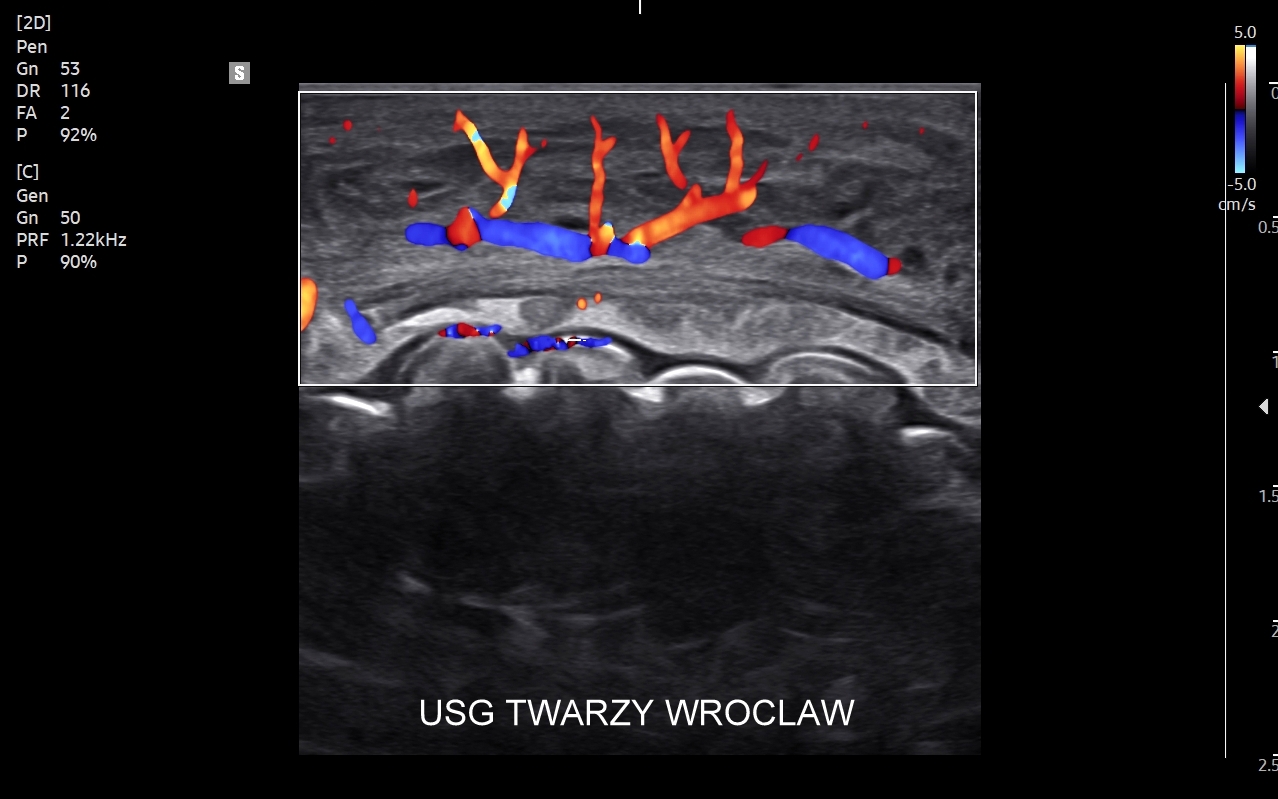

Dr Tomasz Szczepański zajmuje się kompleksową opieką medyczną nad swoimi Pacjentami. W ramach Interdyscyplinarnej Pracowni USG Wrocław wykonuje szereg uzupełniających się badań, zarówno klasycznych, jak USG jamy brzusznej, USG tarczycy, USG piersi, pełen zakres diagnostyki USG Doppler, jak i wysokospecjalistycznych, w tym badania multiparametryczne (MPUS), badania USG z kontrastem (CEUS), ocena przetok dializacyjnych, badania USG Doppler przepływów nerkowych, czy badania USG twarzy